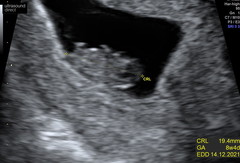

My scan was good too - we saw the heartbeat this morning, measuring exactly what I thought, 7+5. We're now discharged from the EPU, and waiting for the 12-week scan. I cried when we saw it!